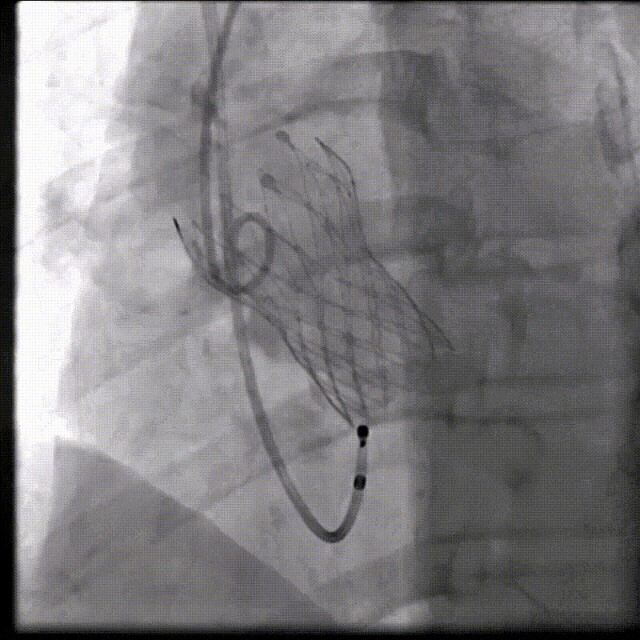

河南省胸科医院心血管内科八病区张由建教授团队在院内超声科、麻醉科、护理科等团队通力协作下,成功完成一例冠脉高风险挑战手术。在团队专业、默契的配合下手术顺利完成,TAVR瓣膜植入良好,患者血流动力学得到明显改善,为患者带来更长久生存期受益和更高生活质量。

(1)Type 0二叶式主动脉瓣,瓣环适中,中度钙化,Type 0二叶瓣受瓣口形态及钙化影响,瓣架呈非理想椭圆形展开,对瓣架支撑力与顺应性提出了更高要求,同时该病例合并升主扩张,对同轴性和释放的稳定性提出了更高的要求。因此优先选择支撑性和顺应性兼具的瓣膜,以及较柔软花冠的瓣膜,降低对升主动脉的损伤,小锥角的设计进一步提升了瓣膜在释放的稳定性

综合病例解剖特点及患者年纪,决定使用第二代可回收的自膨瓣,可回收提高容错空间,为了降低冠脉阻挡风险,决定采用平衡收腰设计的TaurusElite 的瓣膜,先使用大鞘鞘芯进行预扩,然后上20F大鞘。